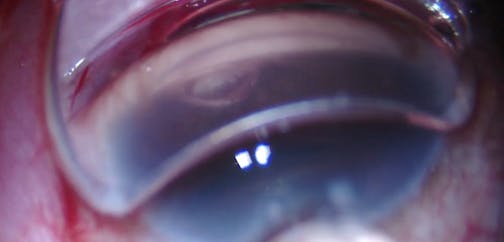

We describe a viscodilation of the Schlemm's canal using the iTrack device (Ellex) over 360 degrees followed by the implantation of two trabecular microbypass stents (iStent, Glaukos). At the end of the case, laminar flow through the aqueous veins help confirm the patency of the device. Presented by Georges Durr.